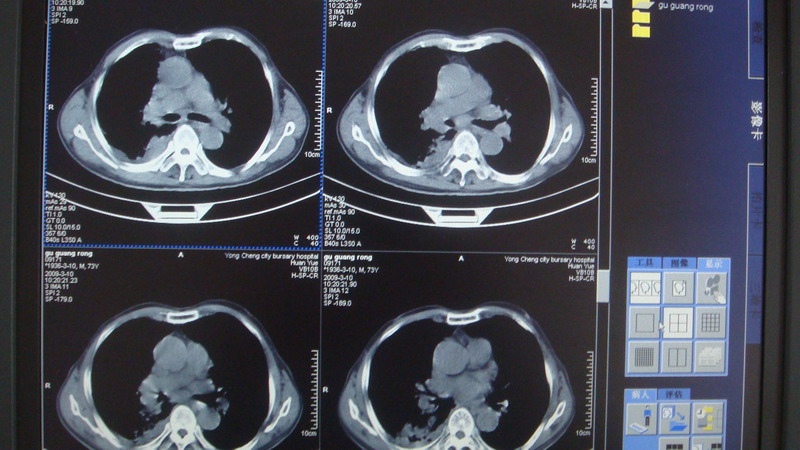

以下是引用光影相伴在2009-3-11 17:27:00的发言:[br]支持 右肺下叶周围型肺癌伴右肺门纵隔淋巴结转移;右上肺继发型肺结核(硬结\\纤维灶);右侧少量胸胸腔积液。另:不排除右侧胸膜转移可能。

以下是引用随光逐影在2009-3-11 16:57:00的发言:[br]支持 右肺下叶周围型肺癌伴右肺门纵隔淋巴结转移;右上肺继发型肺结核(硬结\\纤维灶);右侧少量胸胸腔积液。另:不排除右侧胸膜转移可能。

以下是引用草之原在2009-3-11 19:03:00的发言:[br]支持 右肺下叶周围型肺癌伴右肺门纵隔淋巴结转移;右上肺继发型肺结核(硬结\\纤维灶);右侧少量胸胸腔积液。另:不排除右侧胸膜转移可能。